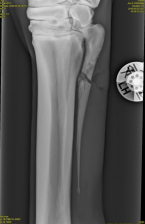

Du tilser en hest med et sår på piben efter et spark og beslutter dig for at tage røntgenbilleder. Du ser derved nedenstående læsion. Hvad er hestens prognosis quo ad tempus?

1 Såfremt tilstanden ikke kompliceres (af eks. gaffelbåndsskade), vil hesten kunne påbegynde træning 4 uger efter operation

2 Såfremt tilstanden ikke kompliceres (af eks. gaffelbåndsskade), vil hesten kunne påbegynde træning 8 uger efter operation

3 Sårfremt tilstanden ikke kompliceres (af eks. gaffelbåndsskade), vil hesten kunne påbegynde træning 12 uger efter operation

4 Hesten vil med stor sandsynlighed ikke komme tilbage i ridning

Det rigtige svar er 3